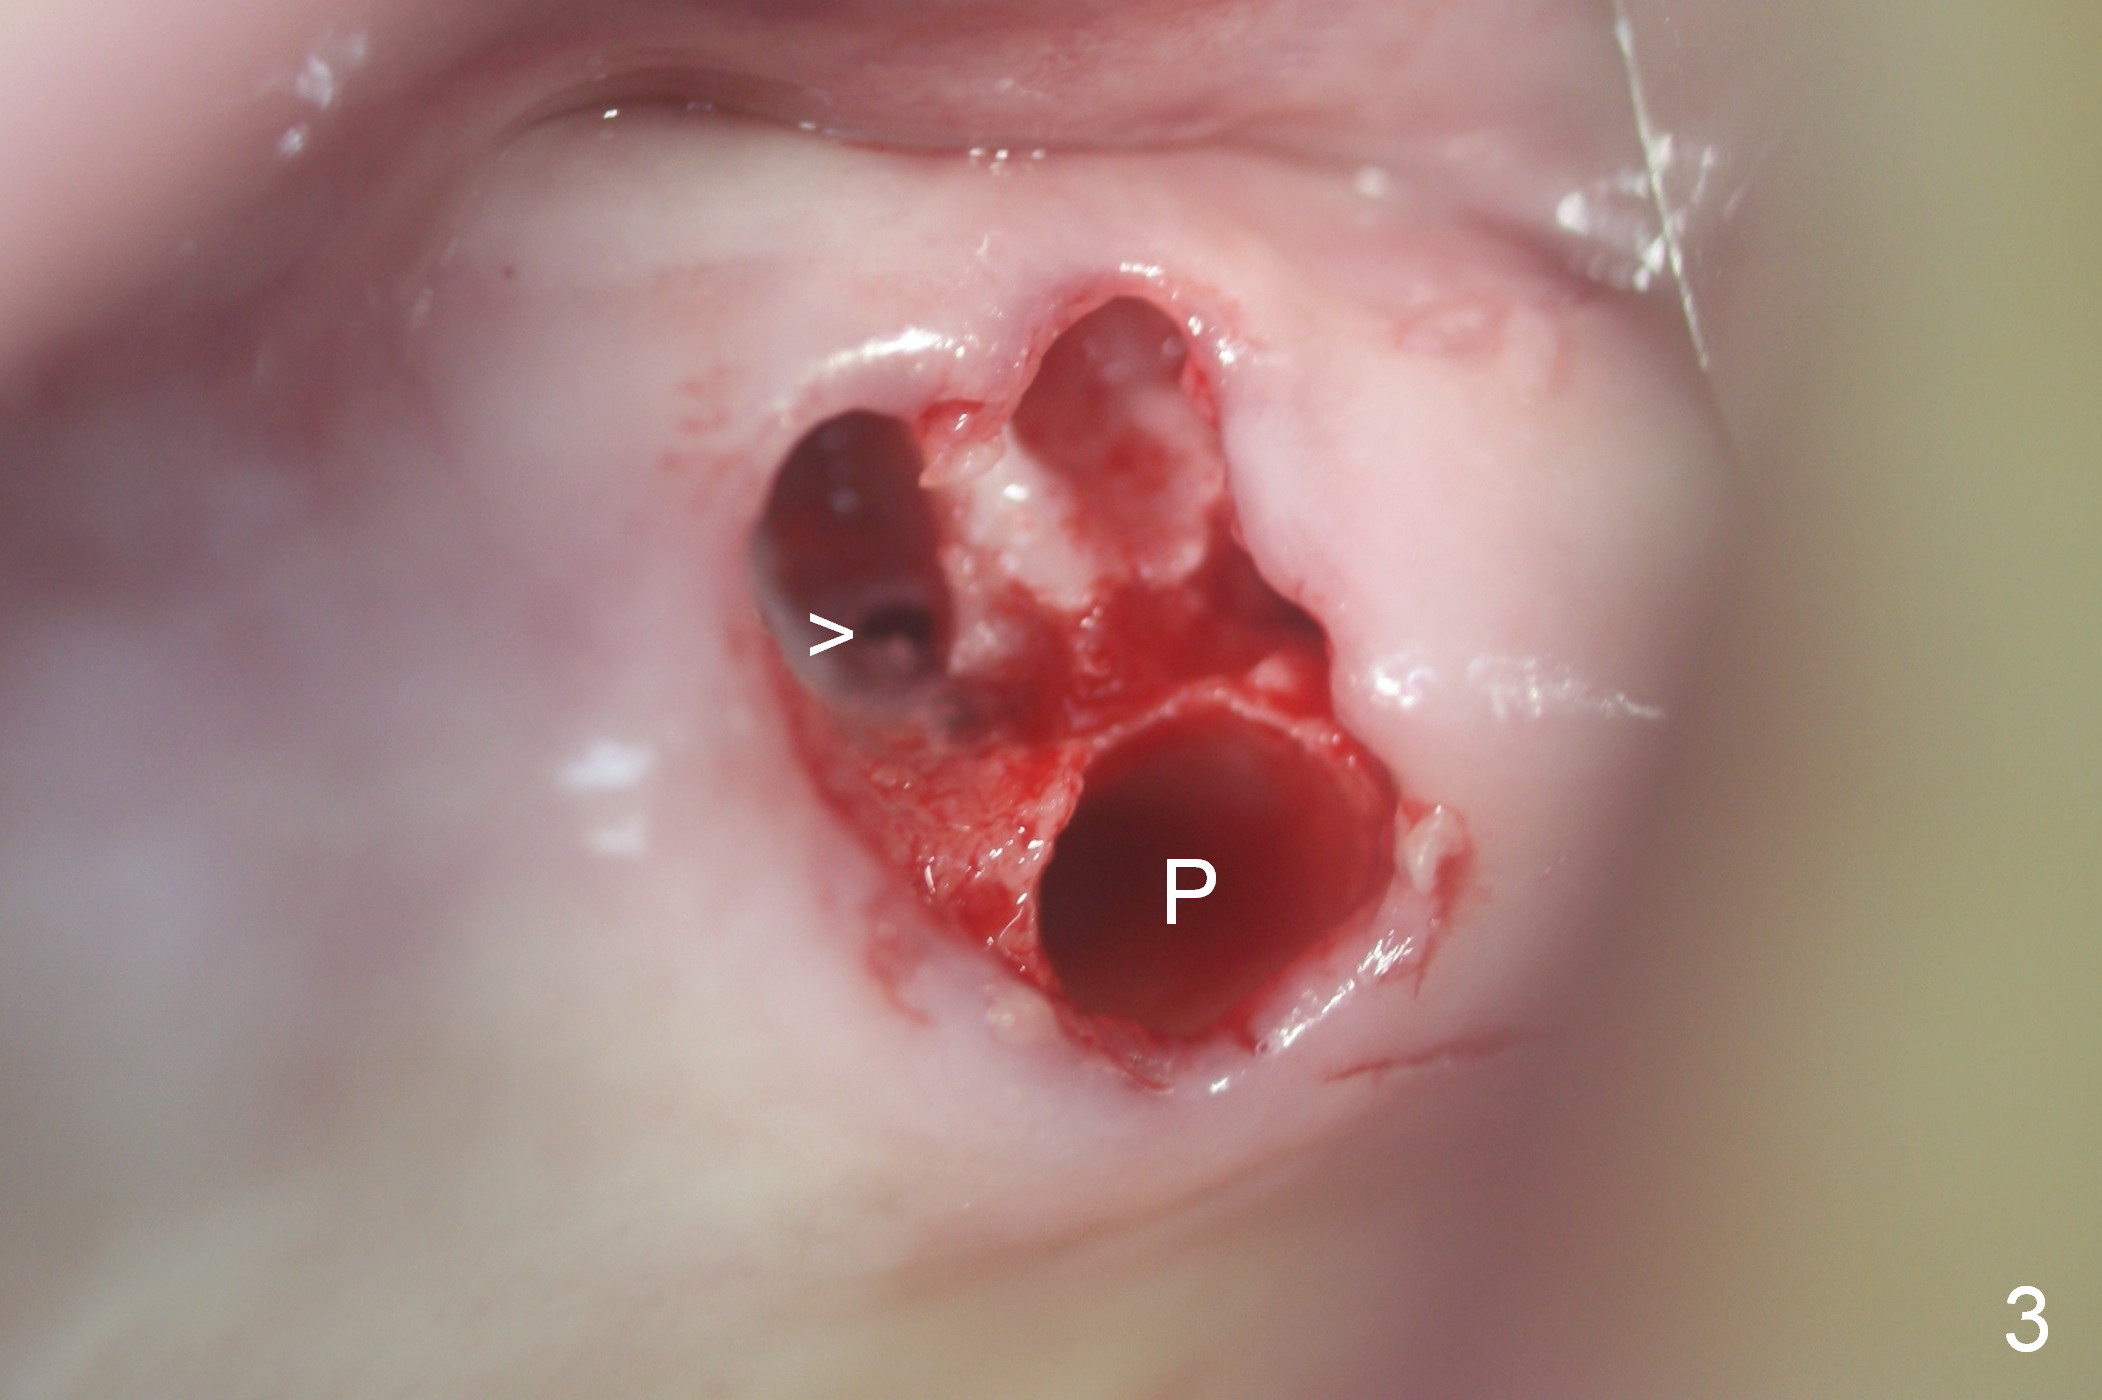

Fig.1,2 show the close relationship of the upper flipper and the residual roots at #15. Atraumatic extraction using periotomes and surgical sectioning still results in perforation of the mesiobuccal socket (Fig.3 >). The distobuccal one is shallow, while the septum is small. It appears that the palatal (Fig.3 P) socket is the most ideal recipient site for the immediate implant and is expanded with Magic Osteotomes until 4.3 mm (Fig.4,5) with the coronal end pushed as buccal as possible. After placing allograft for sinus lift (Fig.6 >), a 5x11 mm IBS implant is placed with insertion torque ~ 50 Ncm. A 6x4(3) mm pair abutment is placed, followed by bone graft in the remaining sockets (Fig.6 *) and by Osteogen plug (Fig.7 *). Finally the socket is sealed by applying acrylic over the abutment (Fig.8). While the acrylic is setting, the flipper is seated and excess acrylic is removed and pushed away from the flipper (Fig.9). Advise the patient not to wear the flipper. If it is being worn, there will be minimal contact between the flipper and the immediate provisional.